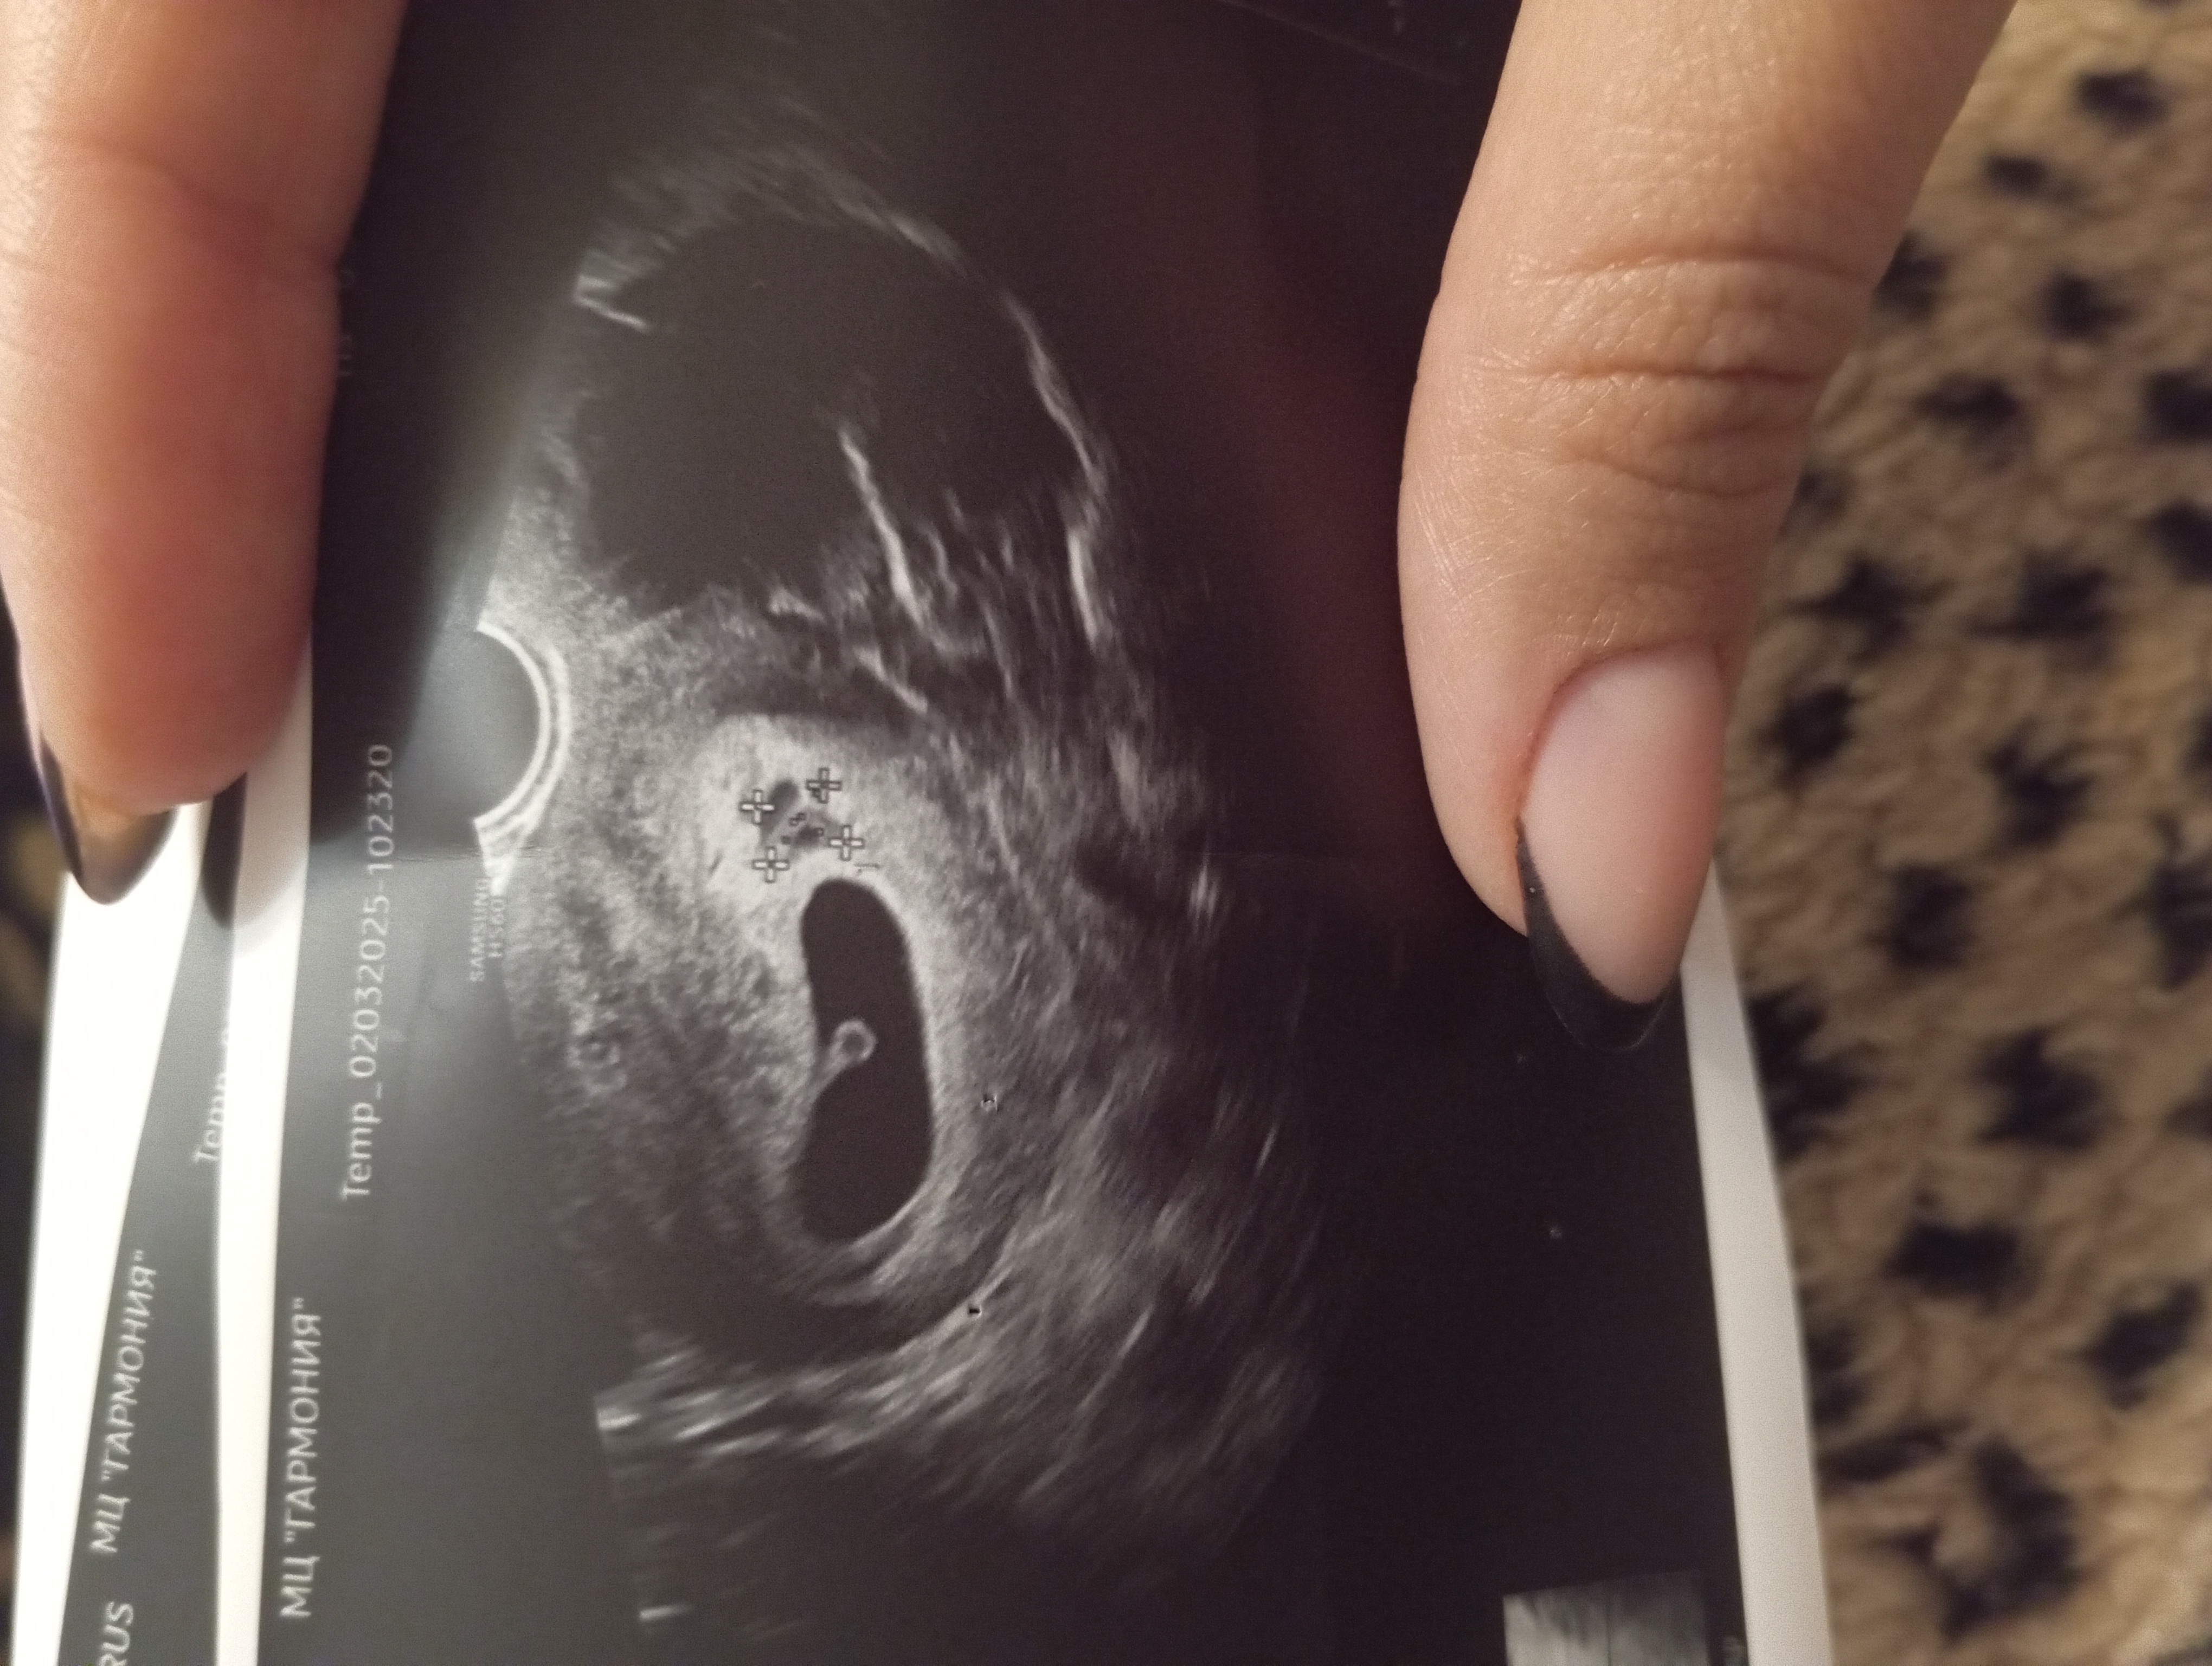

Отслойка плодного яйца

Затрудняюсь с категориейРешила продублировать вопрос в другом сообществе: срок 6.5 по УЗИ, 6.6 по месячным. На УЗИ обнаружили отслойку 10х10мм, пя 23х13мм, ктр 7,4мм, сб +.

Отслойка на фото